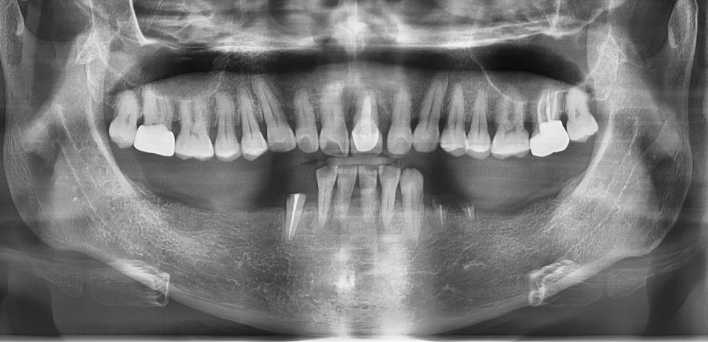

임플란트 : 손 ** 님 (50대)

치아가 있다는게, 아직도 정말 꿈만 같아요.

Before Before

2020.02.30

After After

※ 더서울치과의원은 의료법을 준수하며 위 케이스는 실제 환자의 동의를 얻은 사례로 치료 전, 후가 동일한 환경에서 촬영되었습니다.

환자 케이스에 따라 부작용이 발생할 수 있습니다. 이 부분은 의료진의 충분한 상담과 체크를 통해 예방하고 줄일 수 있습니다.

[임플란트 부작용] 수술 후 관리가 소홀할 경우 출혈, 주위염 등의 부작용이 발생할 수 있어 구강 위생을 철저히 유지하고, 정기적인 검진을 통해 상태를 점검하는 것이 중요합니다.

환자 특징

환자 특징01무치악 상태

환자 특징02수년간 무치악으로 지내심

임플란트가 불가능할것이라

생각하고 내원

위, 아래 6개씩 식립

디지털 풀아치 임플란트